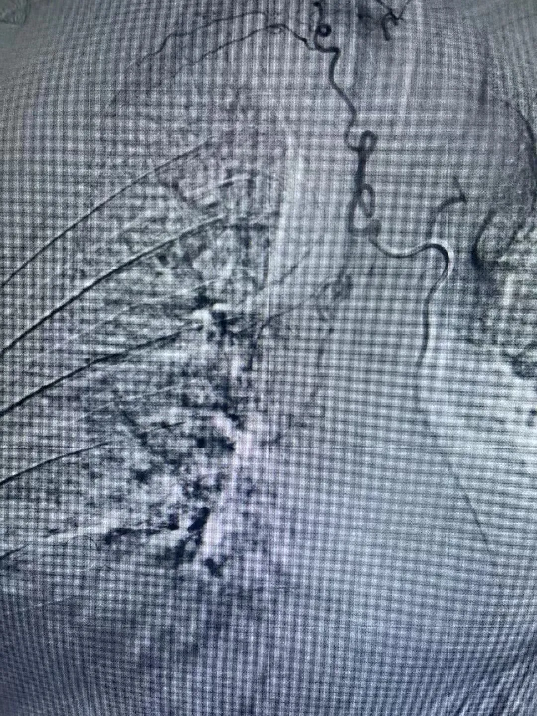

医院呼吸内科团队高度重视患者的治疗,组织全科人员讨论制定个性化治疗方案,通过患者体动脉cta造影检查,明确了包括支气管动脉在内的5支病变血管。经充分术前准备,7月2日晚7点,曹辛瑜副主任在术中精准定位出血病变血管,及时用栓塞剂对病变血管逐个栓塞,完全阻断病变血管血流,痰液立即恢复正常。患者手术顺利,术后恢复良好。支气管动脉栓塞术的应用,大大缩短患者住院时间,且有效降低患者出现大咯血窒息死亡风险。